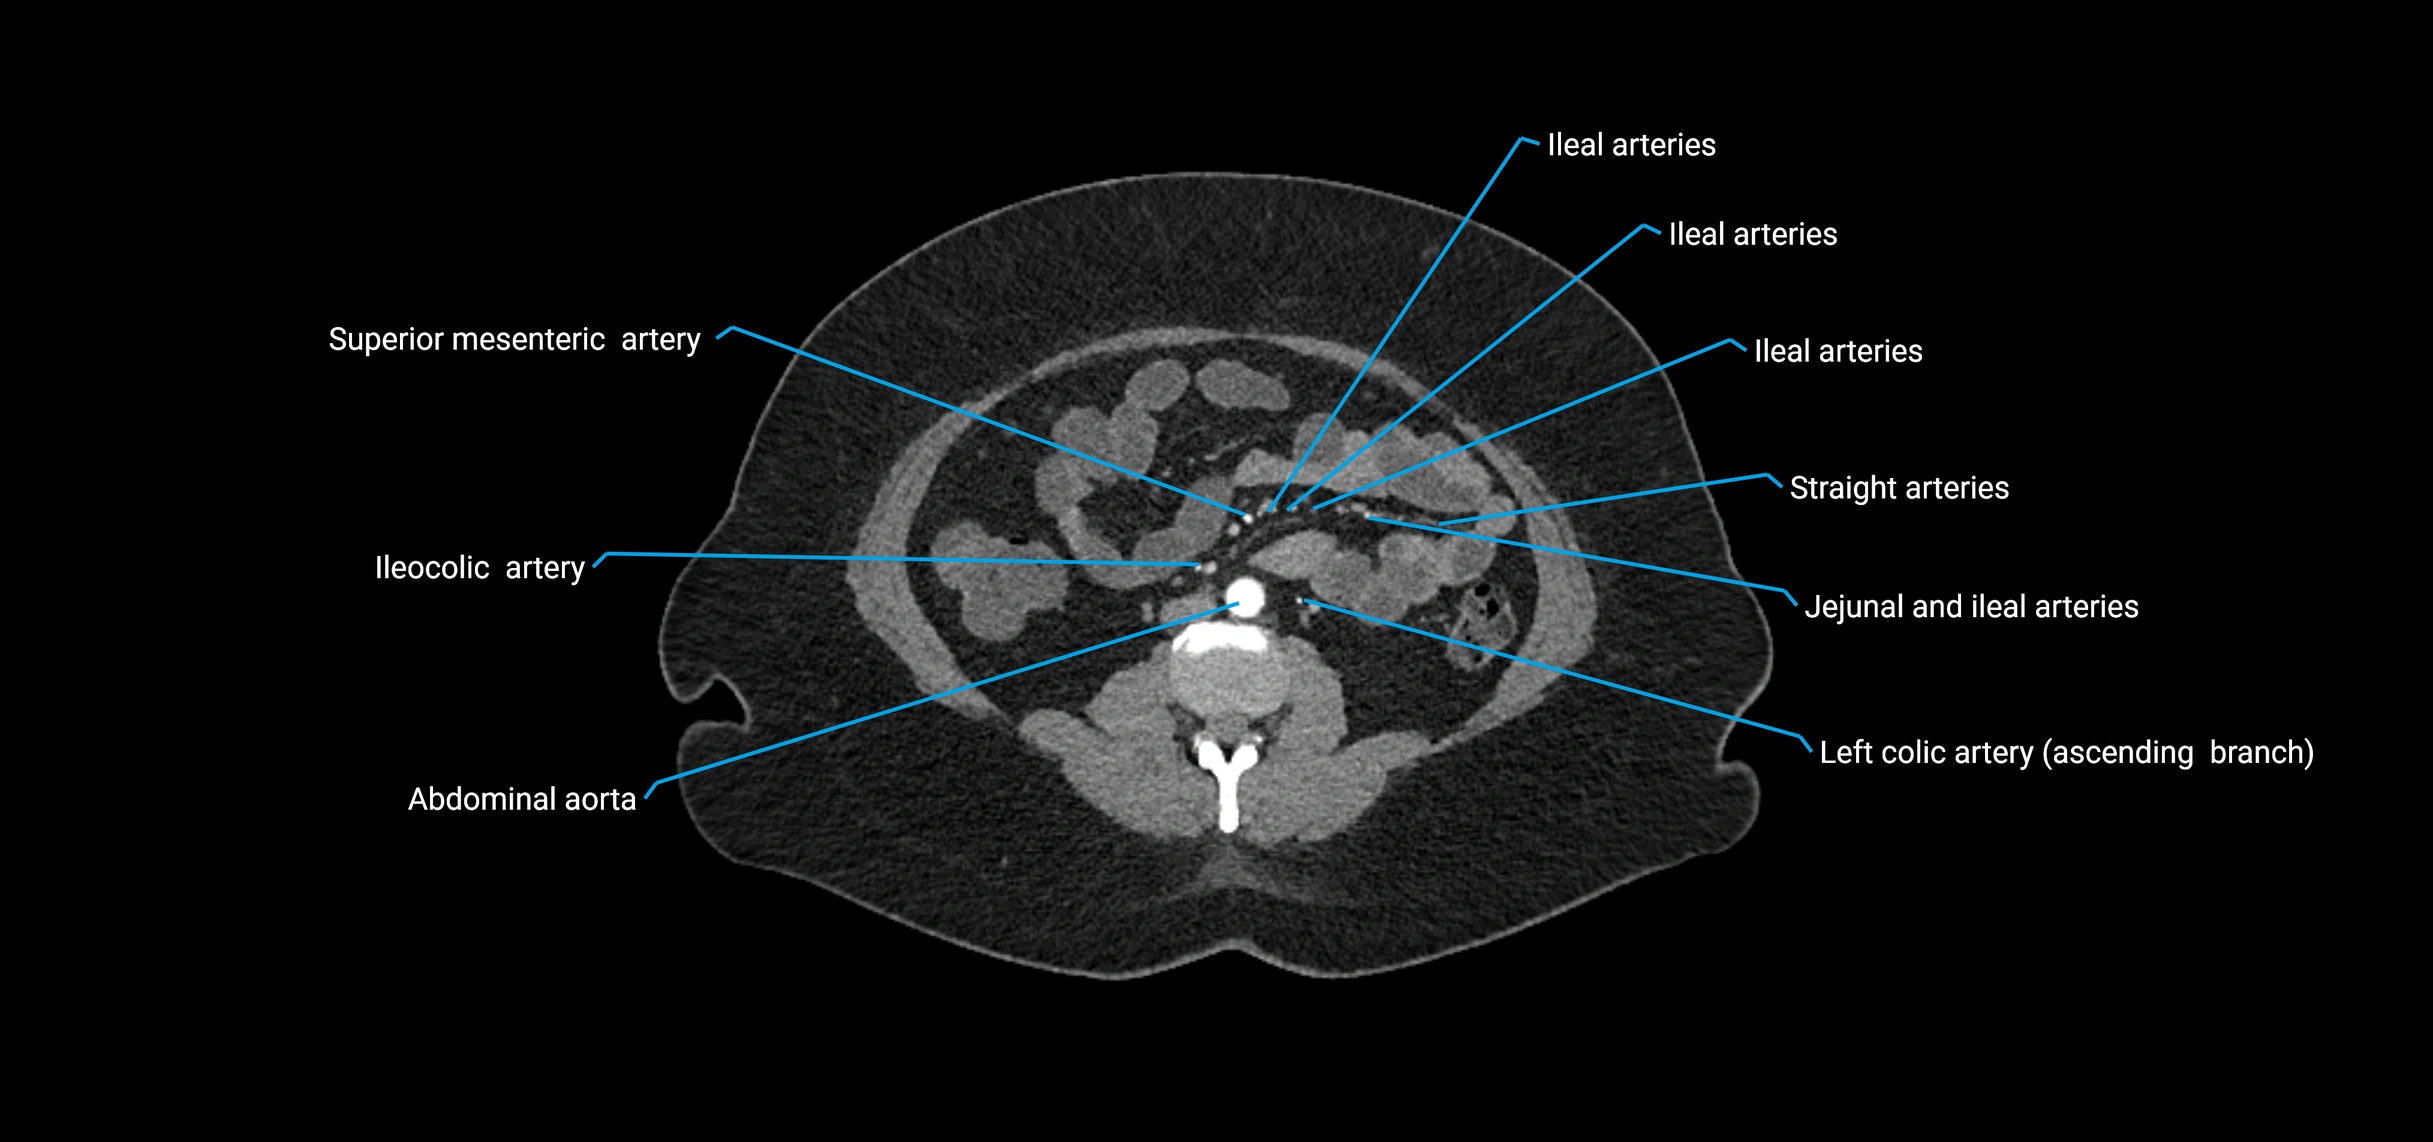

Contrast-enhanced CT (CTA):

• Gold standard for abdominal aortic imaging

• Provides excellent detail of lumen, wall, aneurysm, thrombus, and branch vessels

• Multiplanar and 3D reconstructions help in aneurysm measurement, stent graft planning, and dissection evaluation

• Detects acute rupture, traumatic injury, or occlusion with high sensitivity